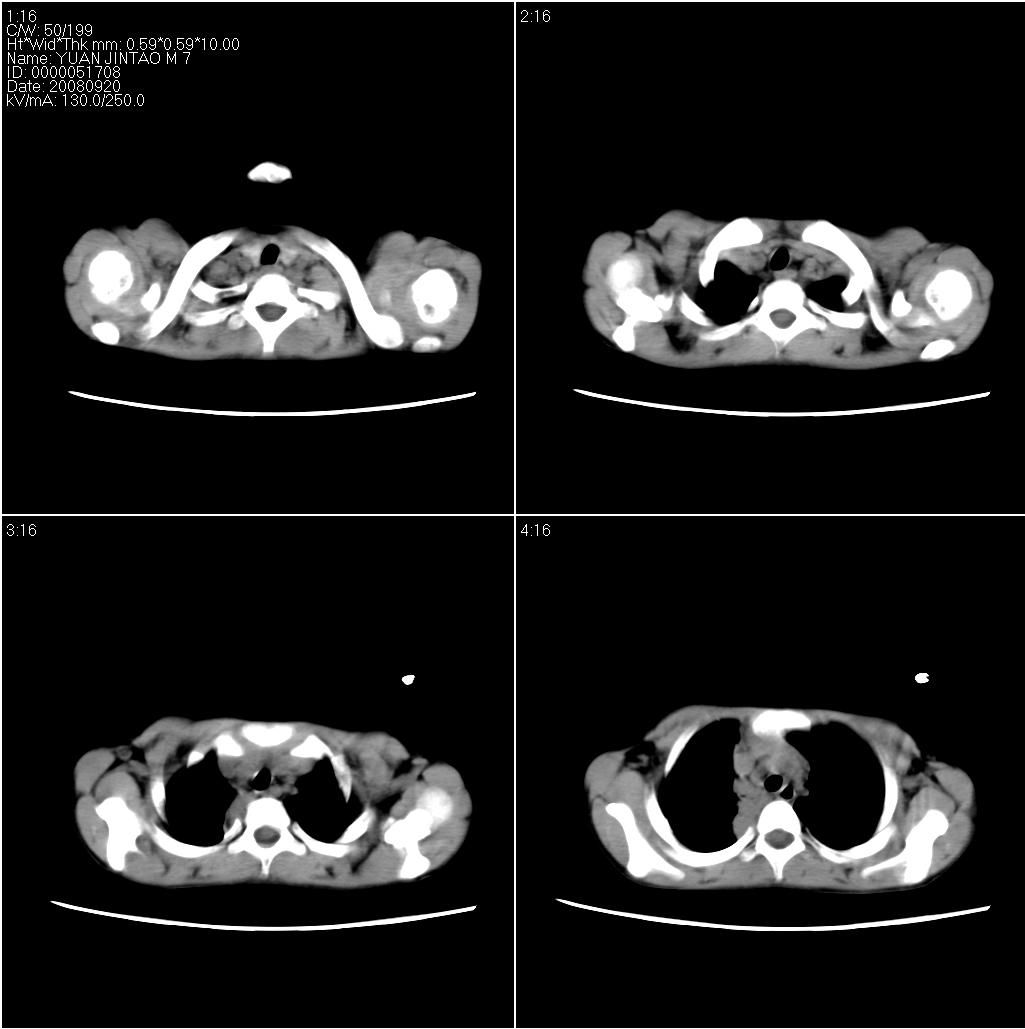

9月20号ct检查情况:

右上肺有班片状条索状高密度影。右肺上叶支气管稍变窄。右前上纵隔有结节状软组织密度影。上腔静脉旁淋巴结肿大。病灶抗炎后扩大。考虑结核可能性大。

右上肺不均匀密度增高,体积变小,水平裂弧状上移,纵隔内有肿大的淋巴结。考虑:

1、右上肺炎(吸收期),纵隔淋巴结肿大压迫右上叶肺膨张不全

2、纵隔淋巴结结核不能排除